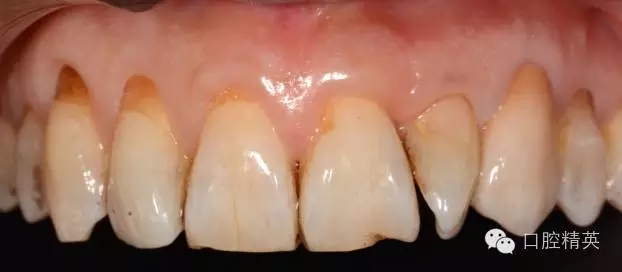

圖12 修復(fù)體代入口內(nèi)正面照